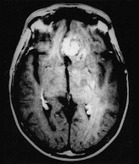

NEURORADIOLOGY Recurrent Glioblastoma Multiforme ...

Recurrent Glioblastoma Multiforme:ADCHistogramAnalysis PredictsResponsetoBevacizumab Treatment1 WhitneyB.Pope,MD,PhD HyunJ.Kim,PhD free survival for the following bevaci-zumab-treated patient subgroups: (a) pa-tients who underwent radiation therapy ... Fetch Doc